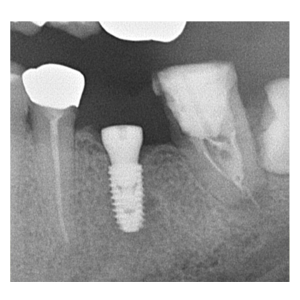

治療途中のインプラント症例

治療途中のインプラント症例です。

歯を失った部分をインプラントで回復したい |